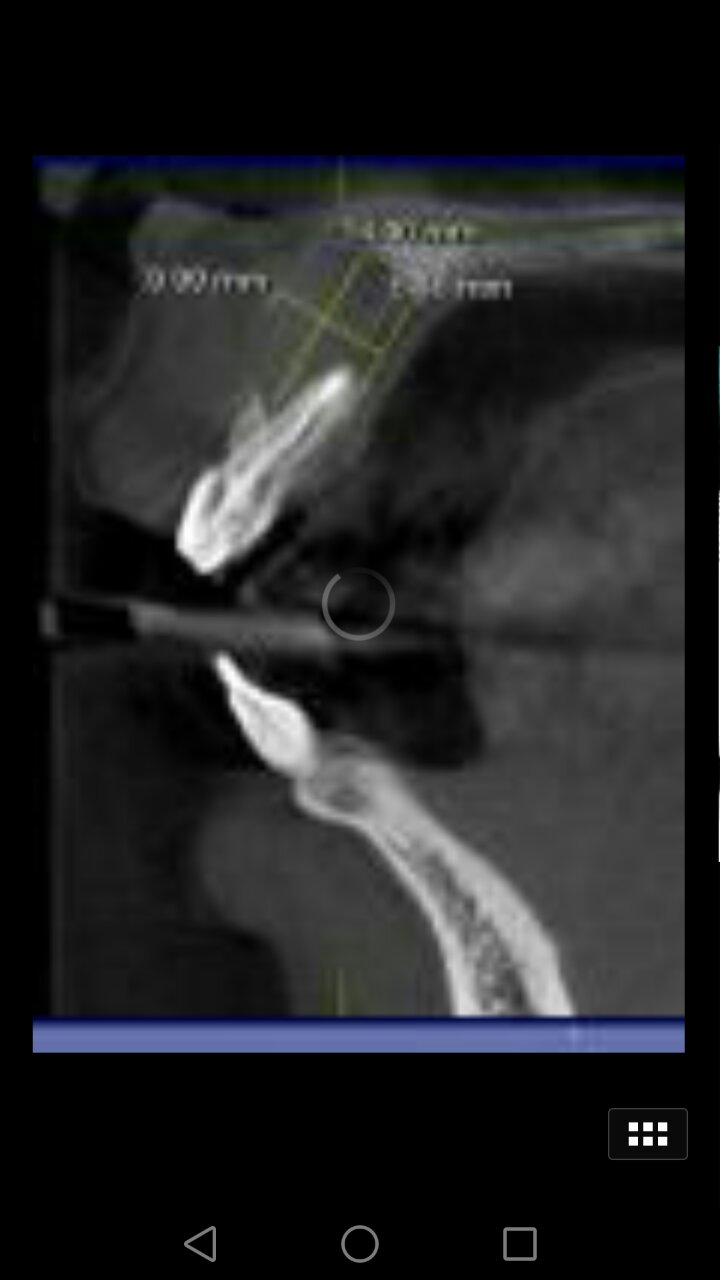

趙幫樹病例

來源于江思玉2群收集整理